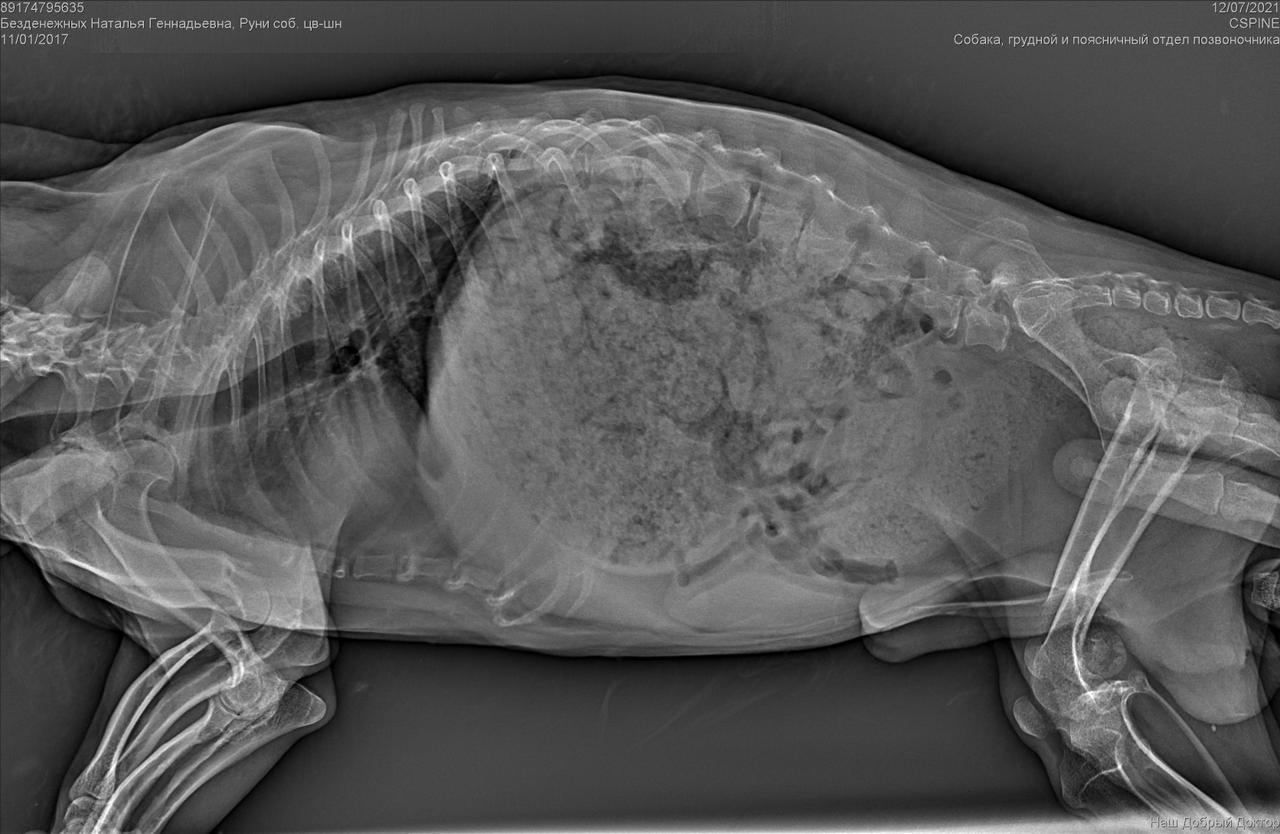

Рентген конечно.....

А нельзя по клиникам уточнить, кто делал резекцию шейки бедра цвергу? Млжет таких хирургов и не так много в городе?

Была травма однозначно. Удалена головка бедра. Мышц нет.

И с позвоночником проблемы. Врачи говорят операции тут не помогут. Если только реабилитация , массаж. Восстановить как то мышцы